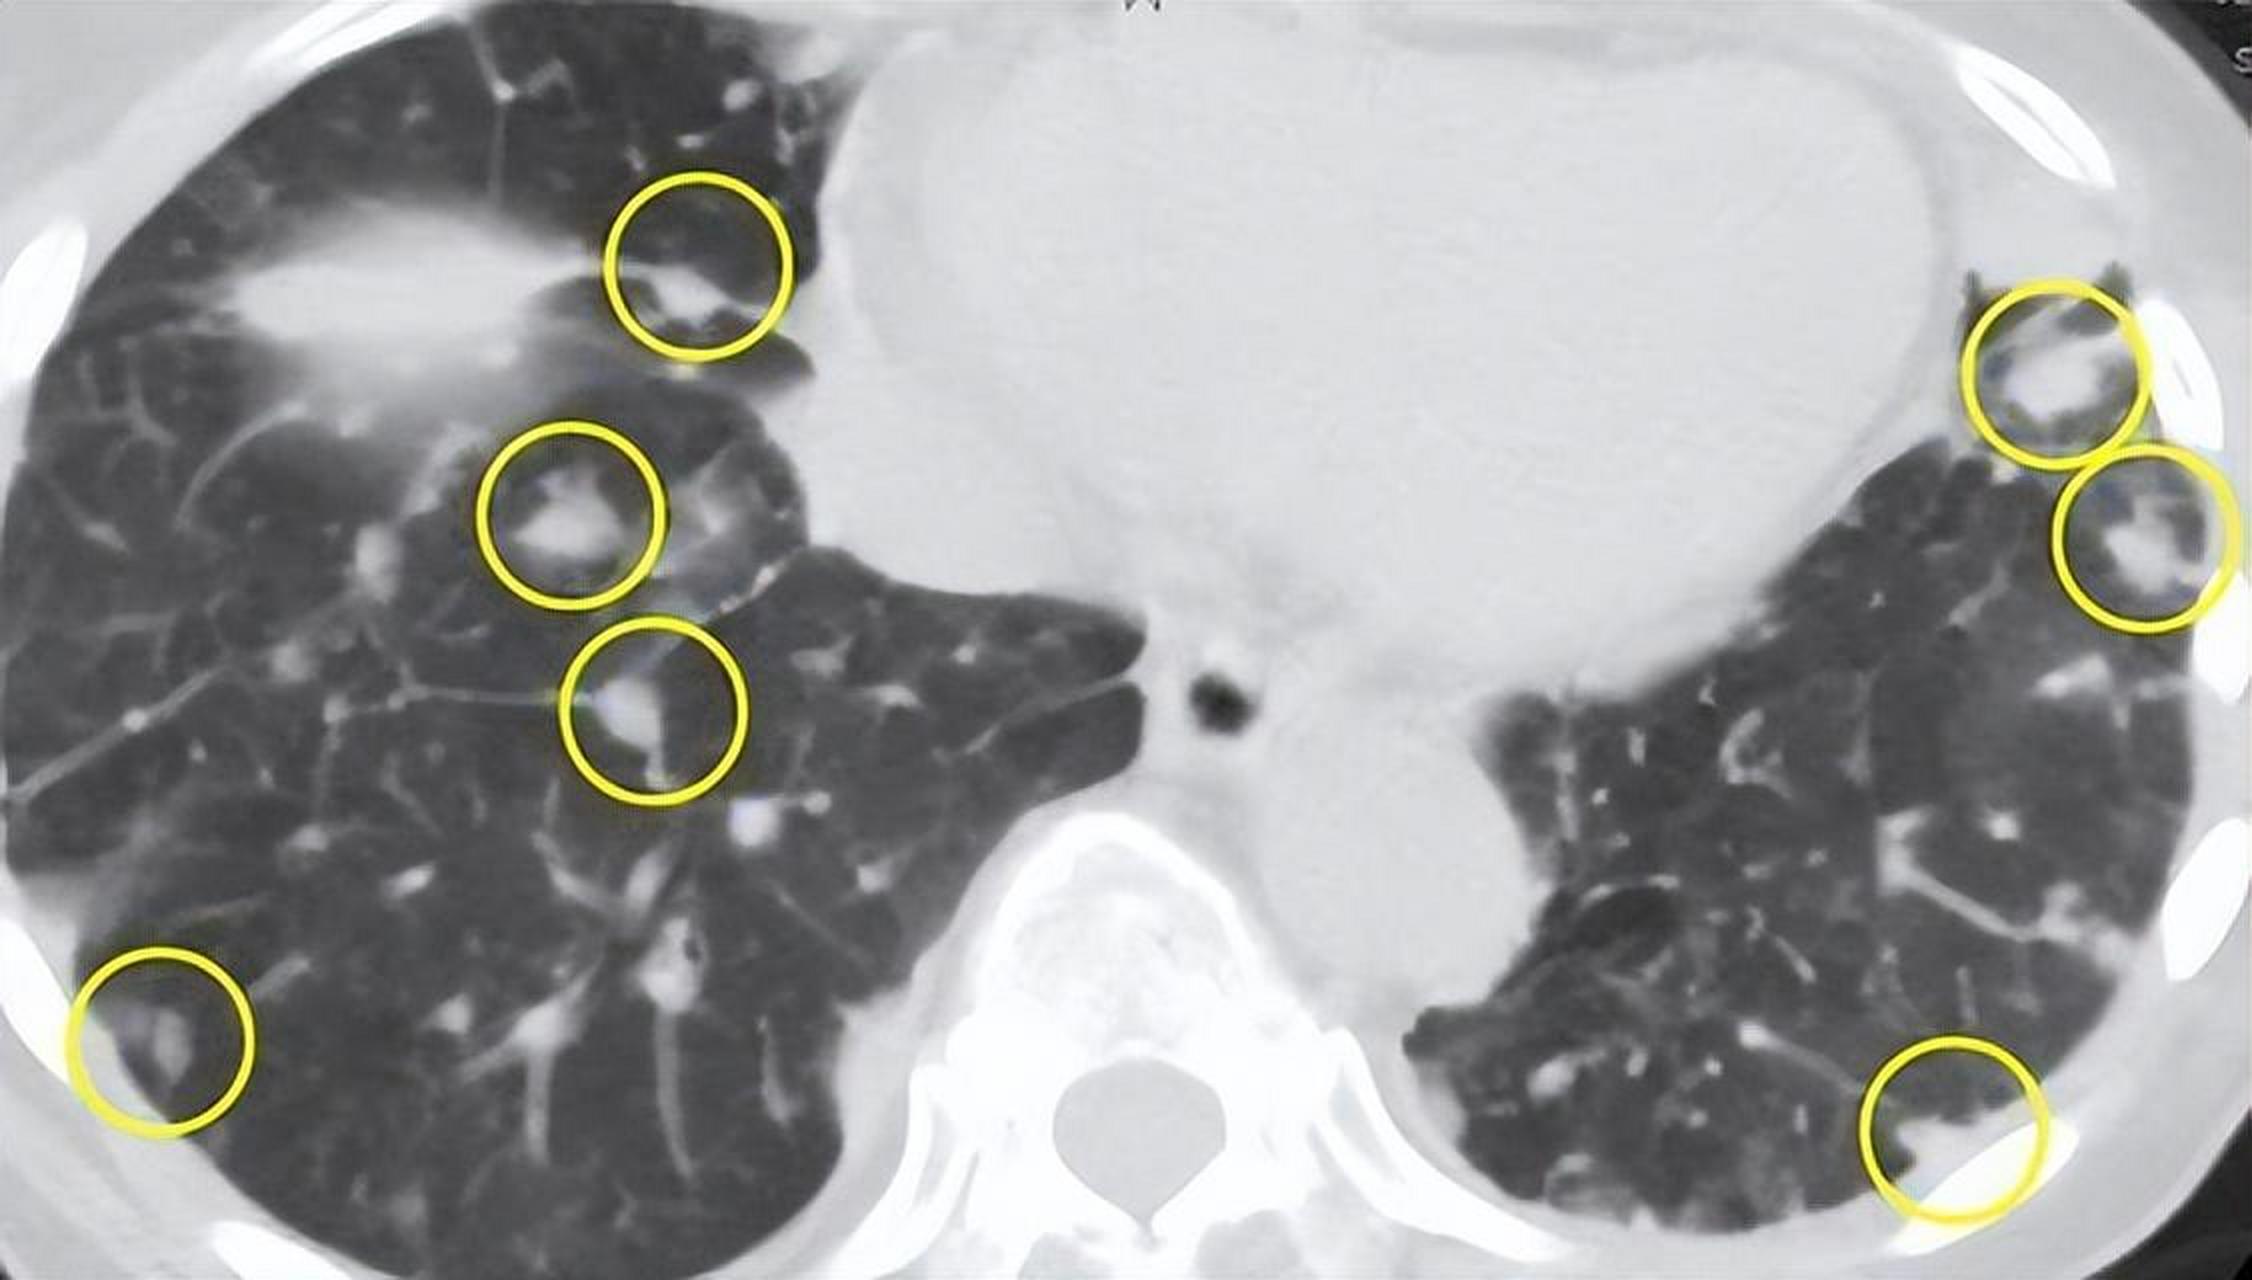

很多人忽略了结节边缘形态变化的重要性。光是结节变大,并不一定代表恶性,但如果出现毛刺、分叶、空泡等影像特征,发生癌变的概率会大幅上升。这类演变,多在两三年内悄然发生。

临床中有不少患者,发现肺结节后便“放任自流”,但高危人群(如吸烟者、长期暴露于粉尘环境者)更应该定期随访。尤其当结节直径超过8毫米,或伴随钙化、空洞等表现时,癌变可能性显著增加。

真正该问的问题不是“我有没有结节”,而是“我的结节,有没有变化”。稳定的结节可以观察,但动态改变的结节,才是诊断的关键。变化包括:大小增长、密度加深、形态不规则等。

总结以上观点,肺结节若开始癌变,极可能会通过咳嗽、乏力、体重下降等方式悄然提示。若同时伴随结节增大、形态改变、边缘模糊等影像学特征,应尽早就医评估。